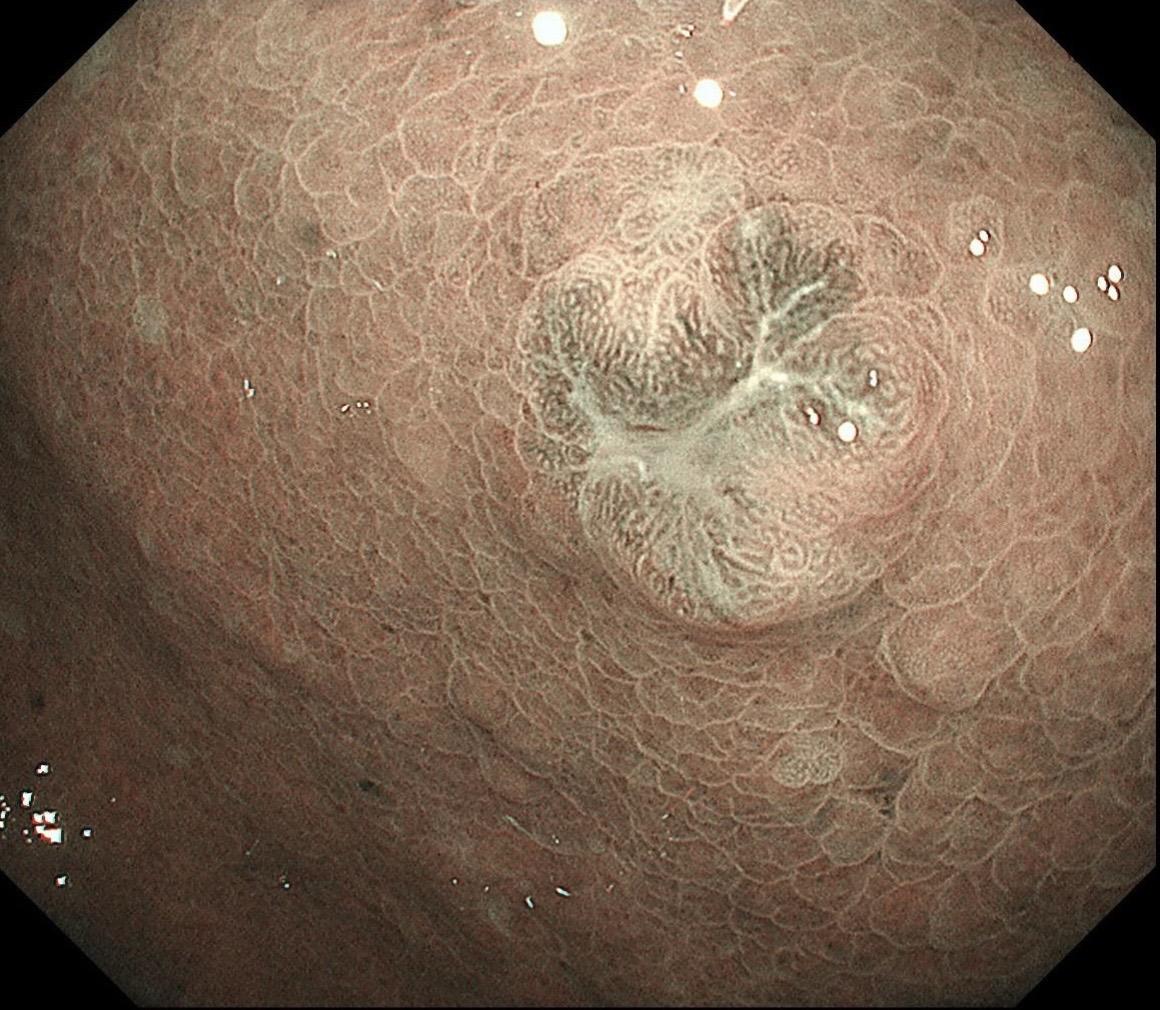

男,70岁,胃底体双发病变。看图猜猜病理呢……尤其胃底这个小的~凹陷性病变,当中央结构观察欠清时,边缘的异常微血管往往有提示作用,哪怕是局部。两处都考虑早期病变,拟ESD微创治疗。